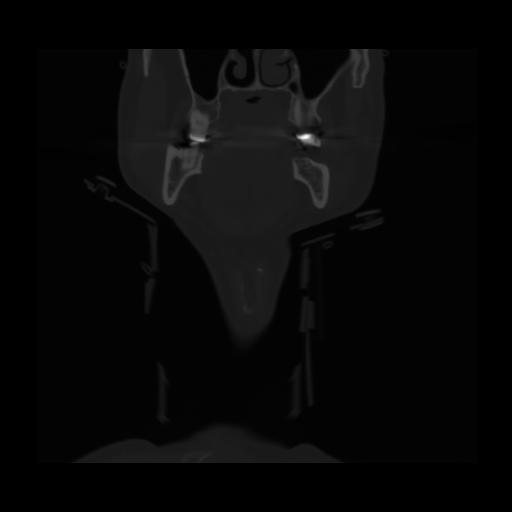

13 P.BLANDAS,,Coronal,2.000,P.BLANDAS,Coronal,